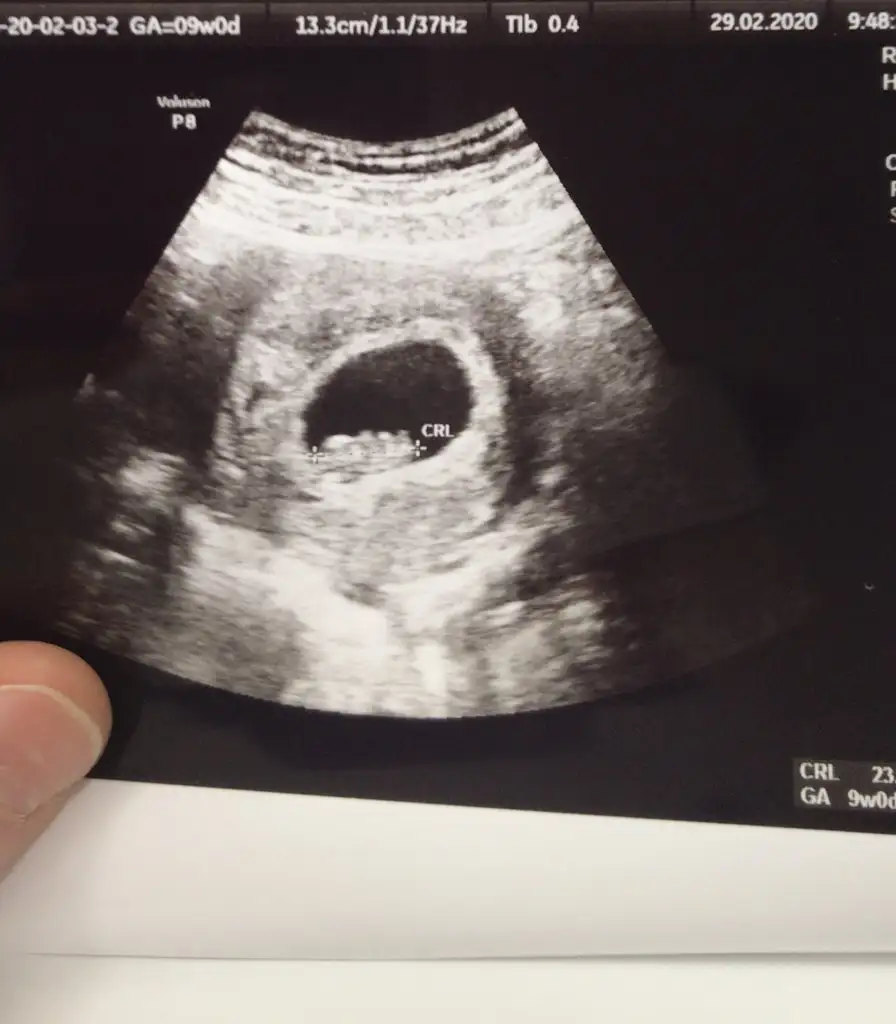

9+2 günlük:)Haftasinida yazman lazim canim![]()

Bu ultrason tam 9.2 günlukse kiza benziyor canim9+2 günlük:)

vajinal mı yapıldı masallah kocaman olmus bile :)9+2 günlük:)

Hayır karından:)vajinal mı yapıldı masallah kocaman olmus bile :)

wayy cok ii benmde persembe 9 hafta oluyo bu kdr büyük görcekmiyim acaba en son 7+3 de görmüştüm fazla net değildi zaten sürekli oynuyo böle net yakalayamıyor doktor :)Hayır karından:)